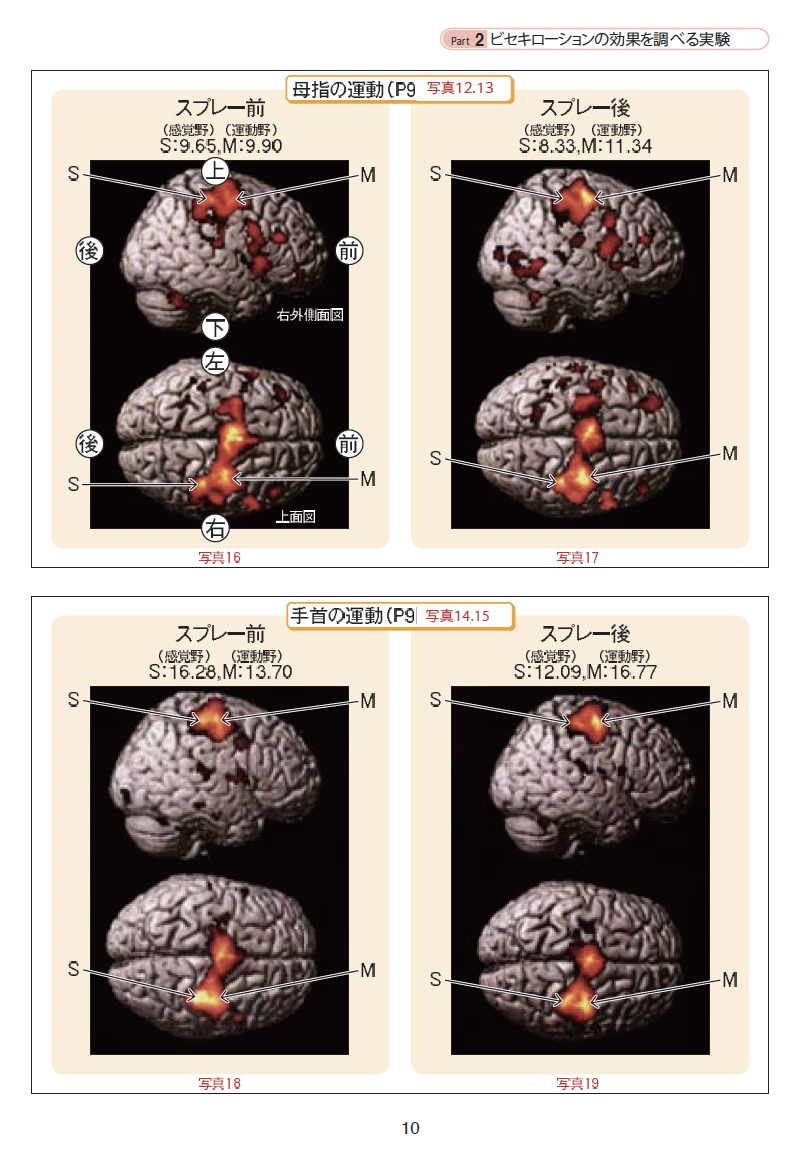

岐阜大学医学部との共同研究 2004年

特殊な液体を手の平と手の甲にスプレーをすると10秒後には母指球筋が13%軟らかくなりその効果が脳に影響を与え脳内神経回路が改善したfMRデーターを臨床で証明しました。この活用法は、寝たきり老人のケアやリハビリ分野への応用、また関節などの比較的浅い部分の慢性疲労や神経痛の軽減に役立つことを岐阜大学医学部及び神奈川歯科大学との共同研究で実証しました。

私が開発したビセキローションのデーターです。

この内容は前の会社で臨床したものです。